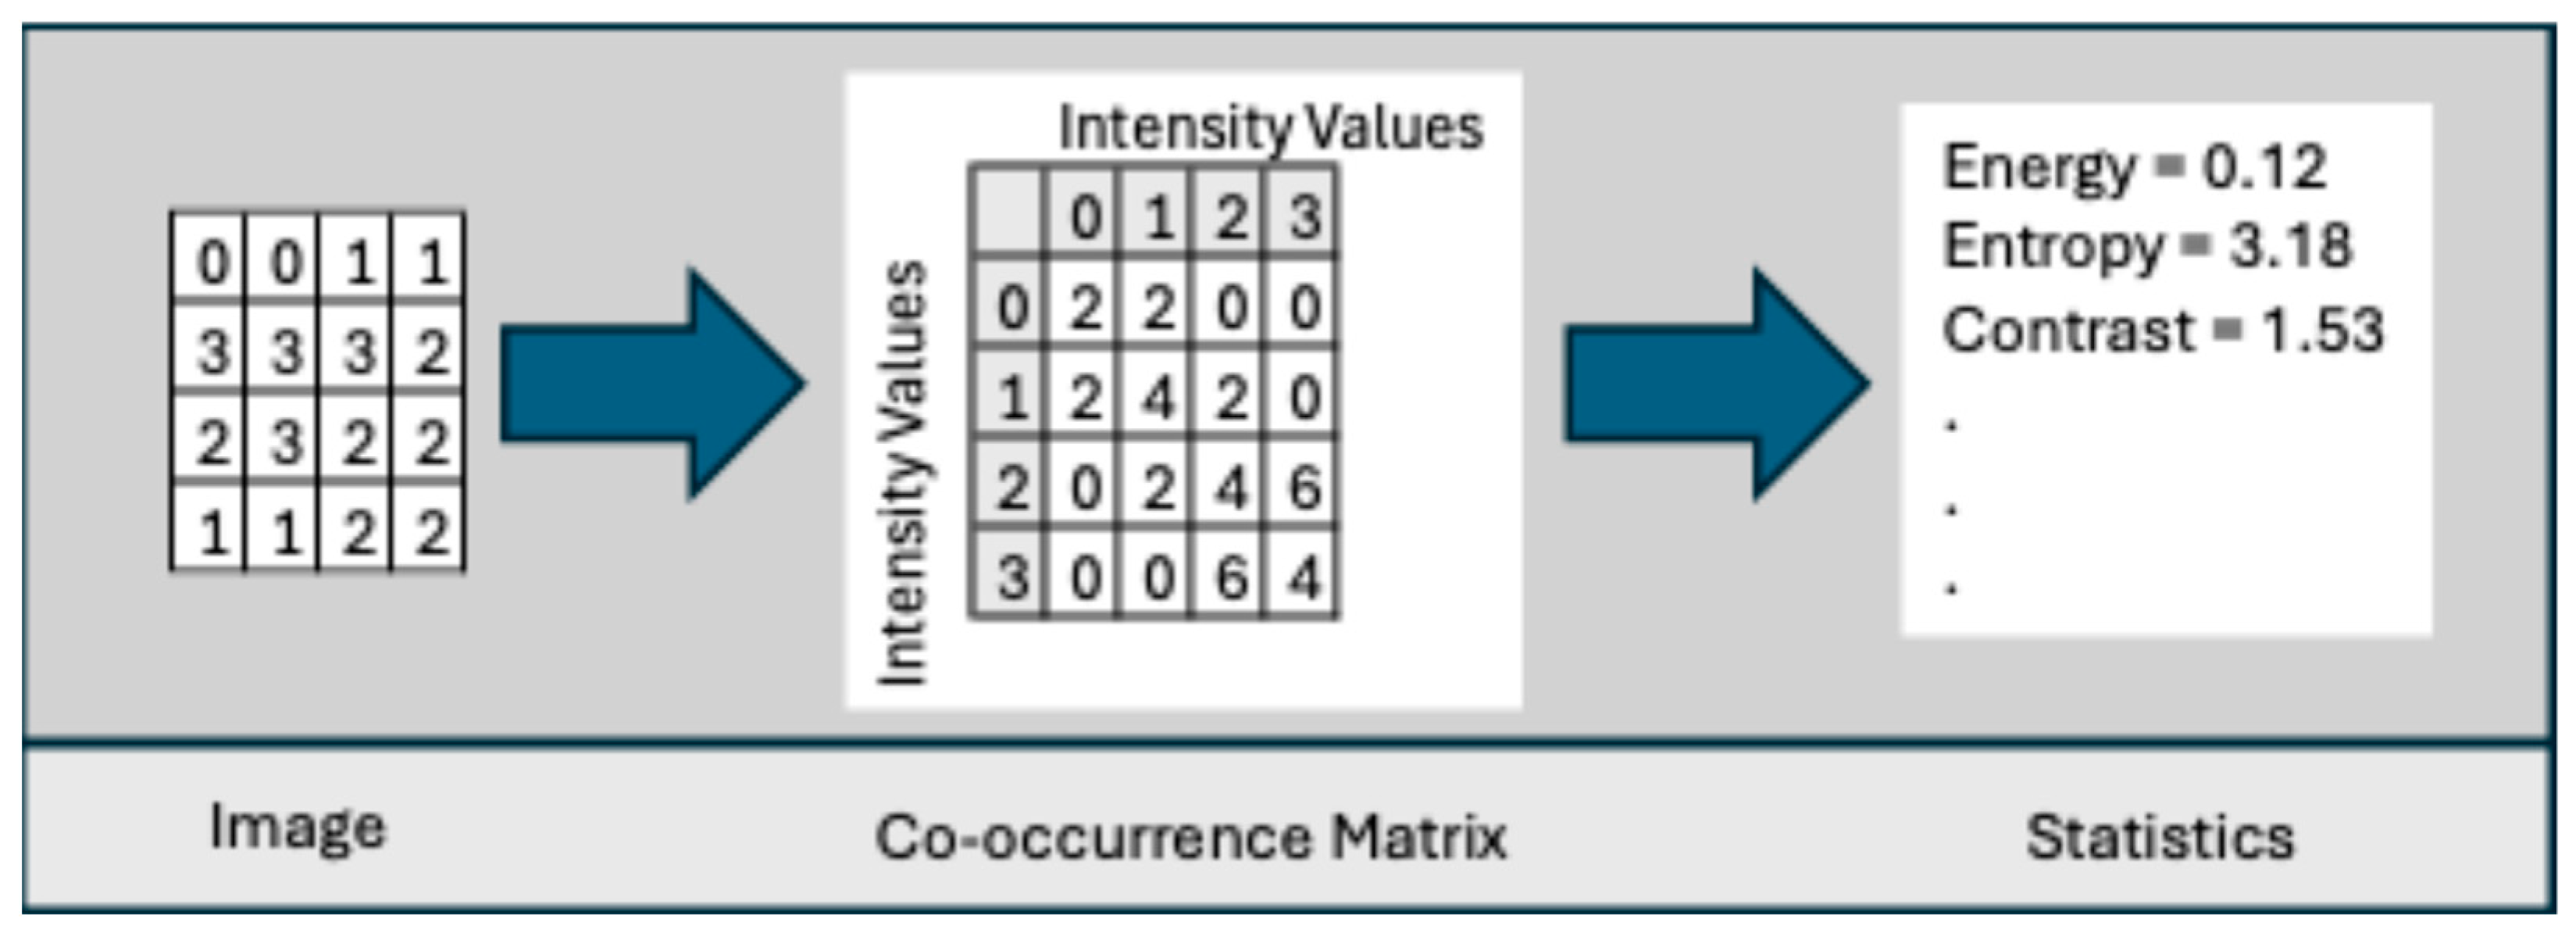

- Co-occurrence Matrix: This was developed by Haralick et al. [78] to codify textural information by calculating second-order statistics on the spatial relationships of gray tones in an image. This spatial relationship is captured in a matrix, called a Gray-level co-occurrence matrix (GLCM) of size . Let g(a,b) represent an entry in the matrix that records the number of pixel pairs in image I that are separated by a specified angle and distance, where one pixel has a gray level of a and the other has a gray level of b. Figure 6 shows the neighboring pixels for all angles of distance 1.